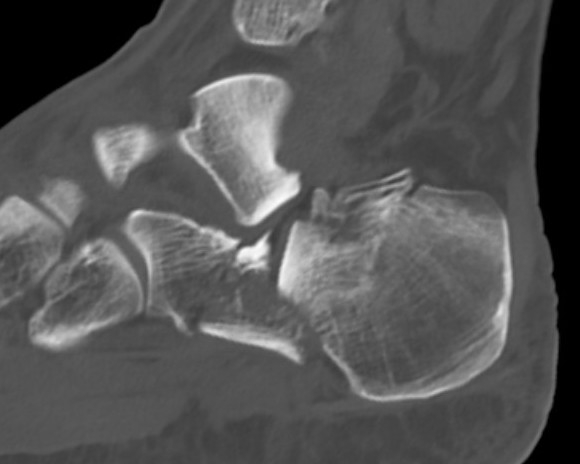

Reduction of subtalar joint

- open lateral wall fragment to access to subtalar joint

- lamina spreader

- reduce and ORIF with screws

- reduce and ORIF sustentaculum fragment